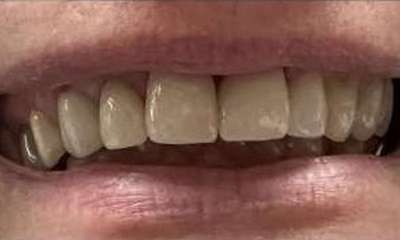

Crowned 10 teeth on the upper arch to transform the patient's smile and achieve their cosmetic goals!